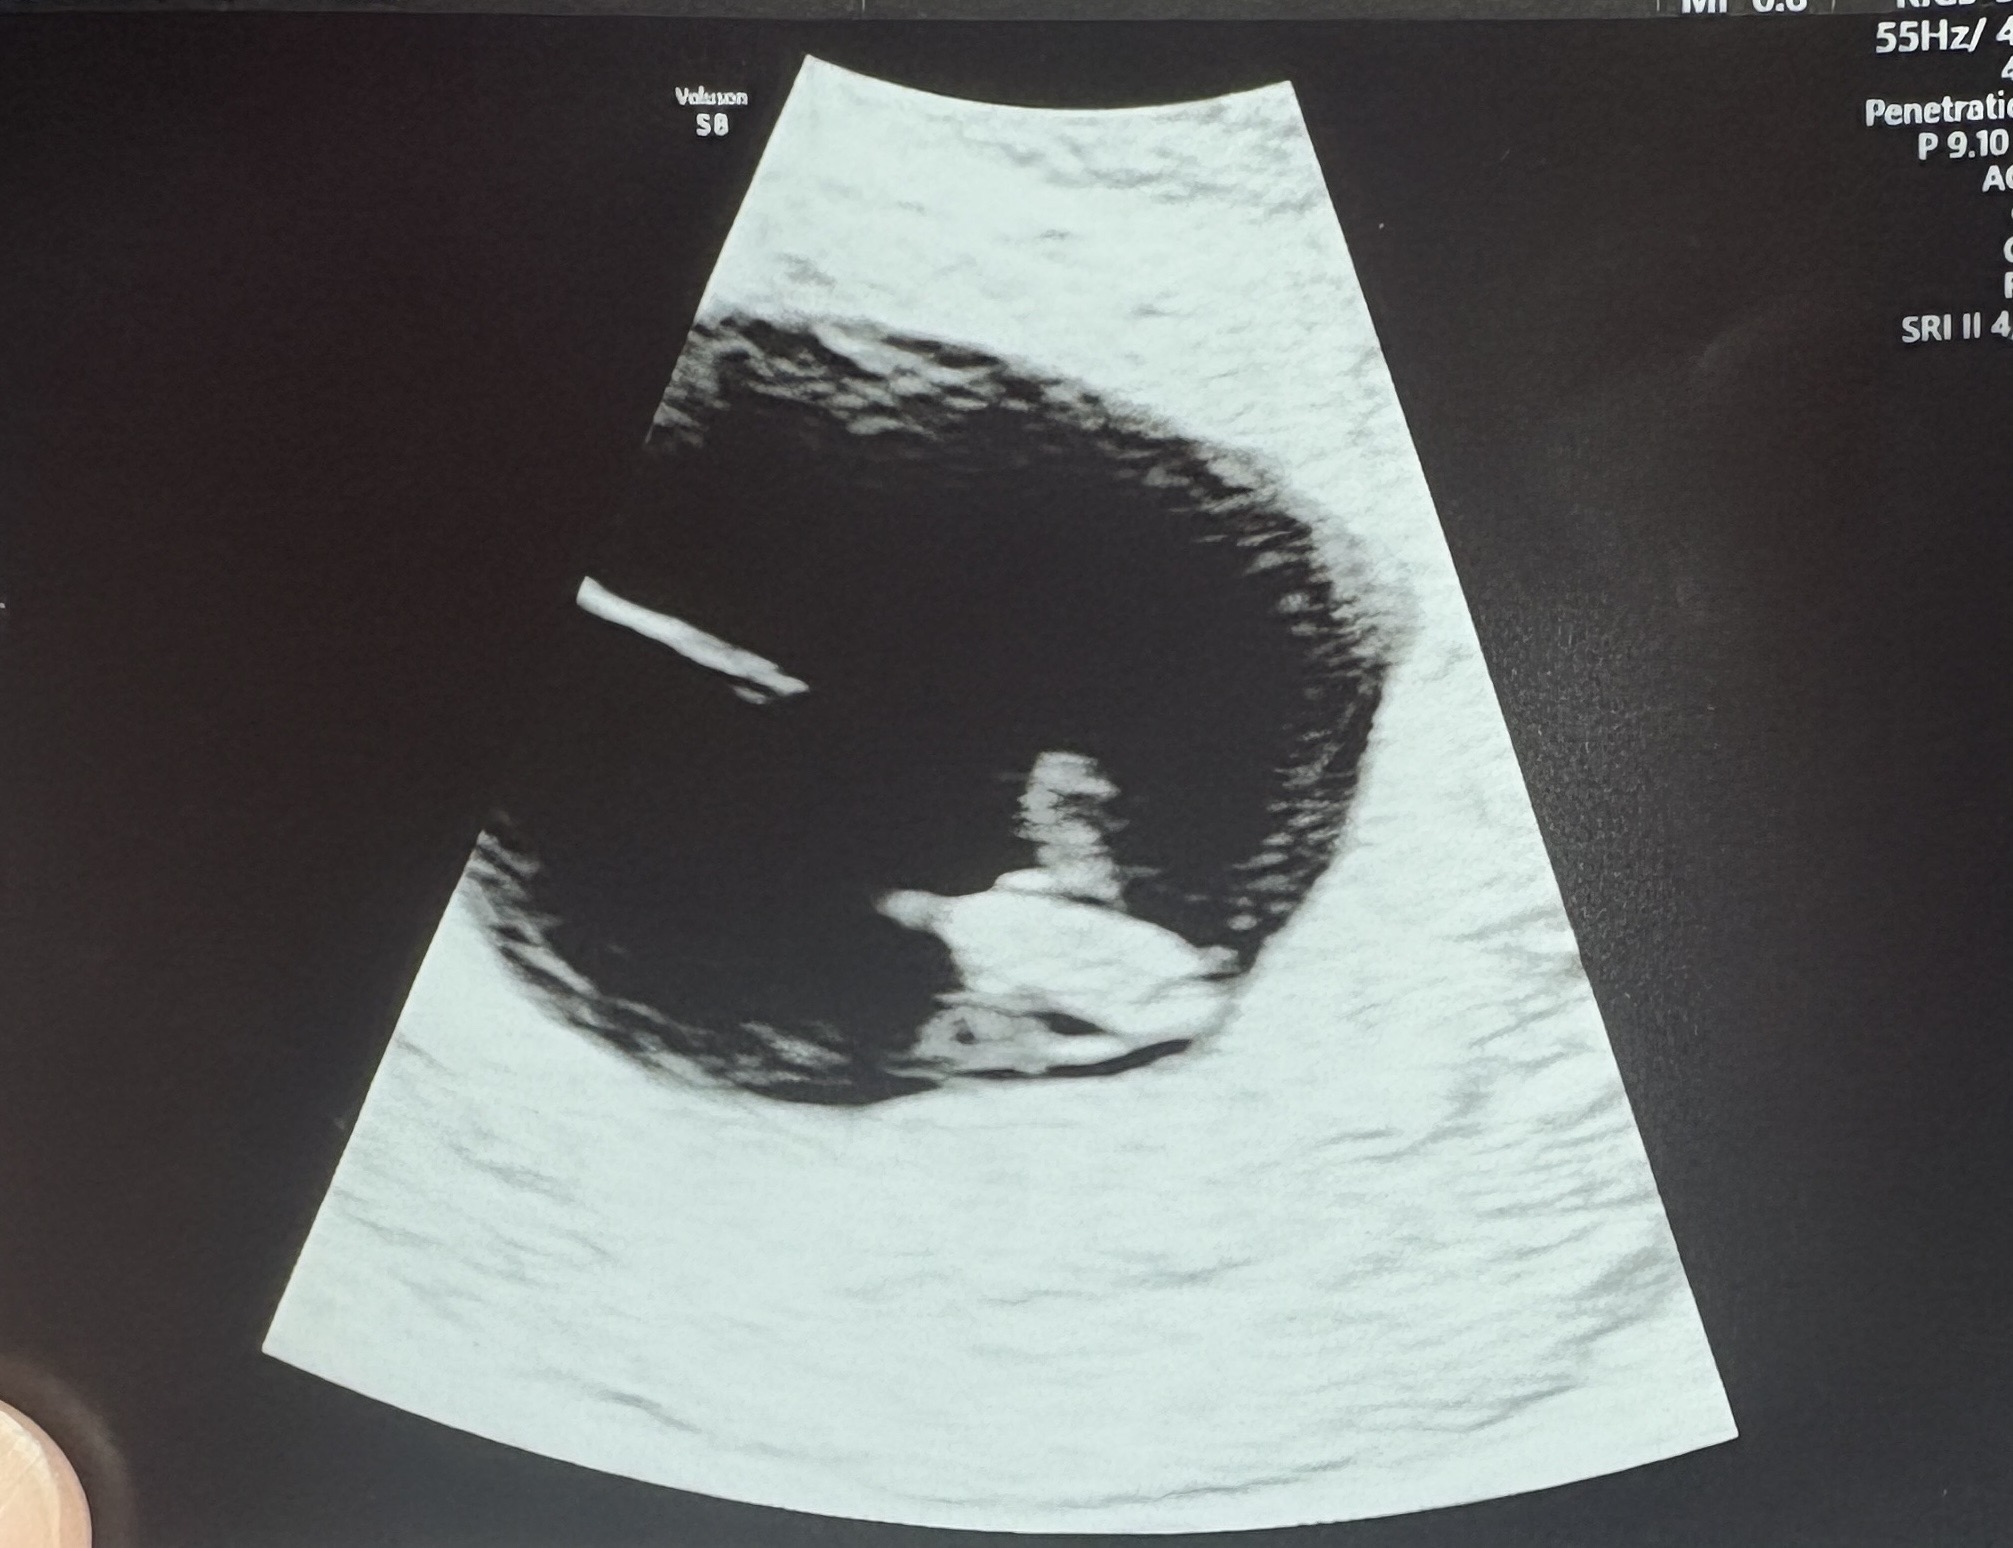

7주차 첫 초음파 보고왔어요

일주일 전부터 계속 속안좋고 재채기도 많이해서 배는 괜찮나 걱정 많이했는데 오늘 드디어 초음파로 보고왔어요! 실제보다 사진이 너무 이상하게 찍혔는데.. 병원에서 난황도 동그랗게 잘 보이고 아기 심박도 130넘고 깜빡이는거 보구 다 건강하다고 하네요 ㅎㅎ 다음 초음파때 까지 기다리려면 또 시간이 엄청 안갈것같은데ㅠ 그동안 속 안좋은거 오늘은 좀 더 버틸 힘이 생겼어요 ㅎㅎ 계속 무럭무럭 자랐으면 좋겠네요!!